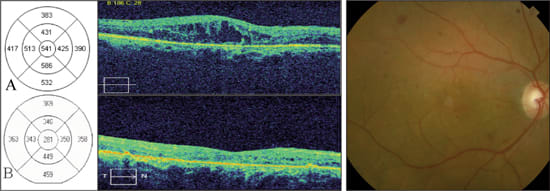

A 60-year-old male with an 18-year history of non-insulin dependent diabetes presented with bilateral decreased vision. His other medical problems included hypertension and dyslipidemia. On initial examination, he was noted to have prior extensive panretinal photocoagulation in the left eye and diffuse macular edema in both eyes. Best corrected visual acuity (BCVA) in the right eye was 20/60+3. SD-OCT revealed cystoid macular edema (CME) with a central foveal thickness of 541 microns (Figure 1A).

The patient was treated with a single intravitreal bevacizumab (1.25 mg/0.05ml) injection in the right eye. At one month follow up, there was no improvement in BCVA or SD-OCT from baseline. The patient was subsequently treated with grid laser photocoagulation directed at the areas of leakage as demonstrated by fluorescein angiography. At two months, best corrected visual acuity was 20/40. SD-OCT showed improved macular edema and a central foveal thickness of 281 microns (Figure 1B). By six months, visual acuity improved to 20/30 and SD-OCT measurements continued to improve despite no further laser treatment.

Figure 1. Sequential SD-OCT images from a 60-year-old male with diabetic macular edema in the right eye. Color fundus photograph shows diabetic retinopathy with macular edema.

A: Horizontal scans through the fovea show loss of the normal foveal contour, diffuse macular thickening, and intraretinal cysts. The retinal map shows a central foveal thickness of 541 μm. Best-corrected visual acuity was 20/60+3.

B: Two months after grid laser photocoagulation, SD-OCT reveals marked improvement of foveal thickness (281 μm) and contour. Best-corrected visual acuity improved to 20/40.